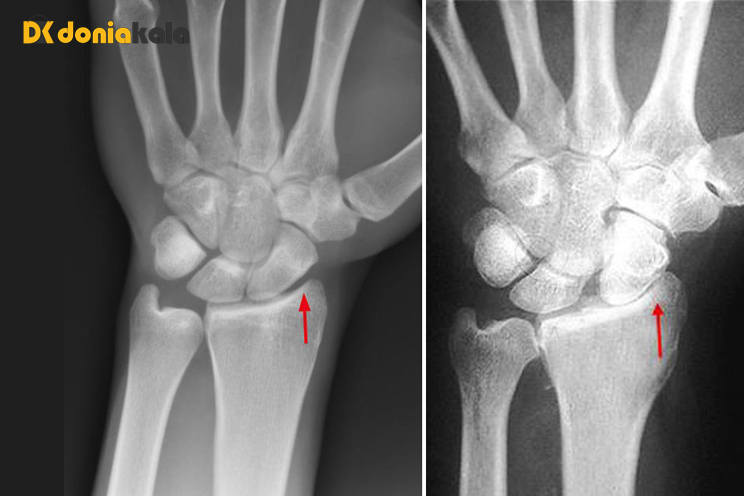

2. آرتریت یا آرتروز مچ دست Wrist osteoarthritis:

افراد مبتلا به آرتریت/ آرتروز مچ دست درد، تورم و سفتی مچ دست دارند. آرتریت روماتوئید، آرتروز و آسیب های مچ دست می توانند باعث التهاب در مفصل مچ شوند. آمپول های استروئیدی، آتل مچ دست و داروهای ضد التهابی می توانند درد و تورم را کاهش دهند. به ندرت، افراد برای بهبود دامنه حرکتی و کاهش درد نیاز به جراحی دارند.

آرتریت/ آرتروز مچ دست چیست؟

آرتریت باعث درد و التهاب در مفصل مچ دست می شود. بسیاری از استخوان های کوچک مچ دست شما را تشکیل می دهند که دست و ساعد شما را به هم متصل می کند. مفصل مچ به شما کمک می کند دست خود را خم کنید، صاف کنید و بچرخانید. آرتروز در مچ دست شما باعث تورم و التهاب دردناک در این مفصل می شود.

انواع آرتریت/ آرتروز مچ دست:

می توانید در نواحی مختلف مچ دست دچار التهاب مفاصل شوید. ارائه دهندگان مراقبت های بهداشتی انواع آرتریت مچ دست را برای جایی که رخ می دهد نام می برند، از جمله:

رادیواولنار دیستال Distal radioulnar: آرتریت در جایی اتفاق می افتد که استخوان رادیوس با استخوان اولنا در ساعد برخورد می کند.

میدکارپال Midcarpal: آرتریت در هشت استخوان کارپال کوچک در مچ دست ایجاد می شود.

رادیوکارپال Radiocarpal: آرتریت در جایی ایجاد می شود که دو استخوان ساعد (رادیوس و اولنا) و استخوان مچ دست به هم می رسند.